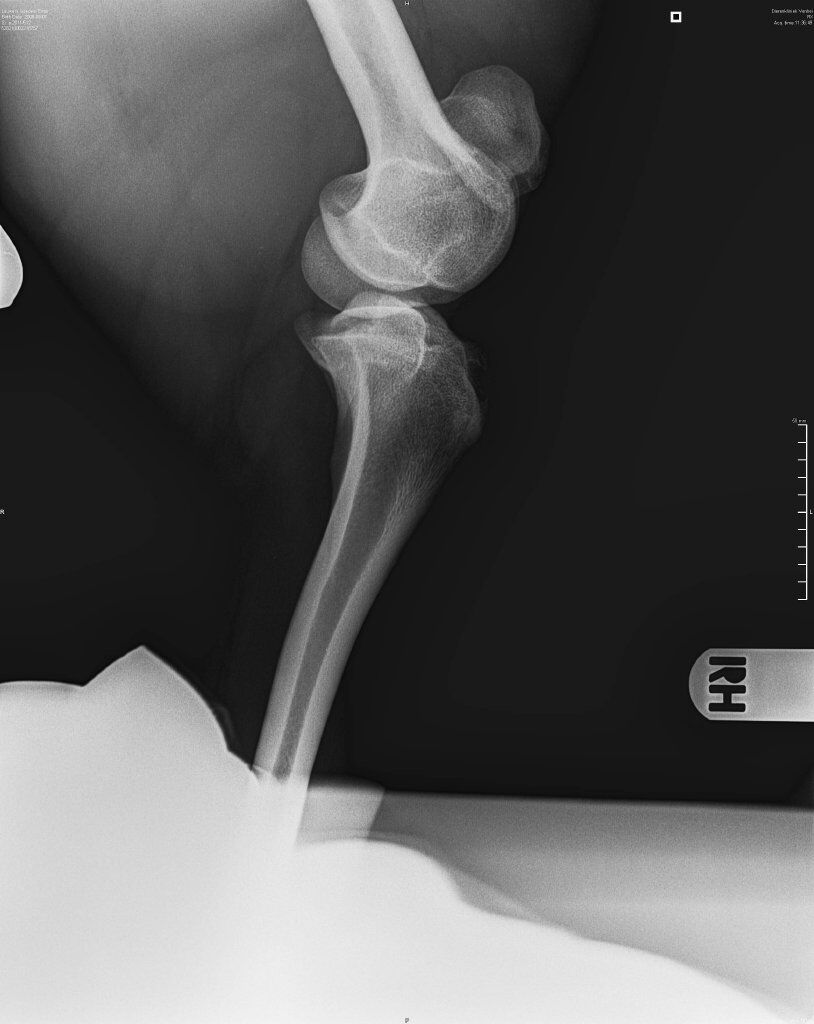

Na een paar stapjes wordt meteen besloten om rontgenfoto's te maken van de knietjes, die zijn met de hand gewoon te luxeren.

Het verdict is niet min : patella luxatie op beide knietjes... ze zijn misvormd en moeten eigenlijk operatief gecorrigeerd worden.

De groeven moeten uitgediept worden, de knieschijf van vorm aangepast en de banden over de knie aangespannen.

In bijlage, foto's van de knietjes... niet zo makkelijk te bekijken/begrijpen als leek